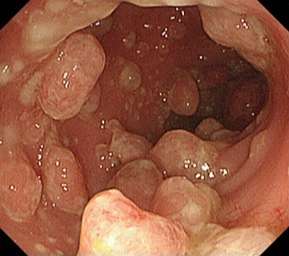

血便が持続するダックスの大腸内視鏡検査(ダックスに多い炎症性ポリープの症例写真)

- 消化管のポリープや腫瘍

- 胃や腸の粘膜の潰瘍やびらん

前述したとおり、内視鏡は消化管の粘膜を直接見ることができる点が大きなメリットです。粘膜の色やただれ、出血、隆起などを目視で確認できるため、画像診断では見つけにくい異常も的確に捉えることができます。